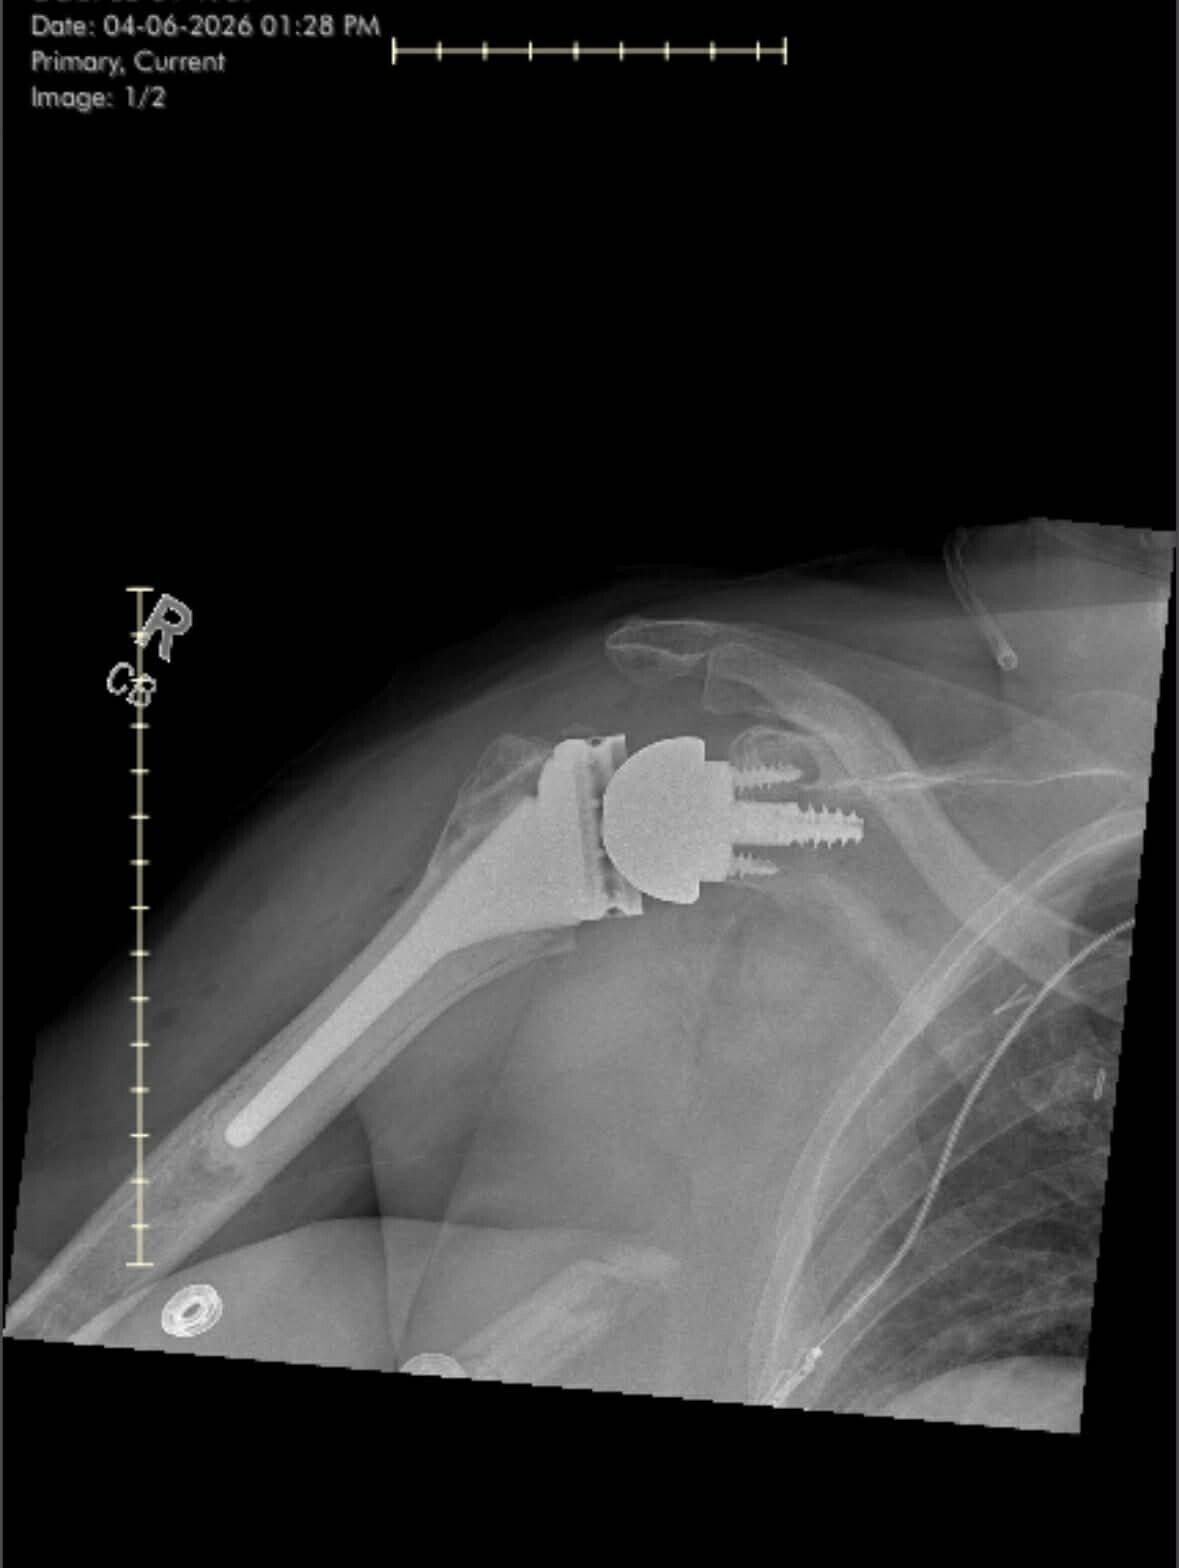

For the past four months (approx. November), I’ve been having problems with my right arm/shoulder. The same one that I broke three years ago on a customers porch during an ice storm ( I work for Shipt a shop and delivery grocery service). Haven’t been able to lift with that arm without hurting. Went to my primary physician. He thought it was rotator cuff injury. He took NO x-rays. Sent me to physical therapy. I went to physical therapy for three weeks for what they thought was “Frozen Shoulder”. It wasn’t getting any better, actually getting worse with each session. The physical therapist then sent me to the orthopedic doctor. I had appointment with him on February 5. They took x-rays. And then told me that I had severe arthritis in my arm/shoulder. Where I had the fracture before. It was very irregular on the ball of my arm, causing me pain. He named some temporary fixes, but it all comes down to I need a total reverse shoulder replacement. I had a CT scan on 2/12. Then we will be setting up surgery shortly after that. Right now probably end of March beginning of April.